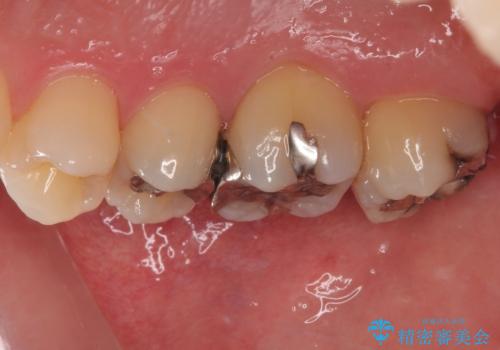

歯列が移動したとはいえ、左右ともに後方傾斜しており、むし歯の除去、形成(形を整える)、型取りの全てが非常に困難な処置となりました。

セラミッククラウンの適合はレントゲン写真からも分かる通り、境界がぴったりと合った、高適合のものとなりました。